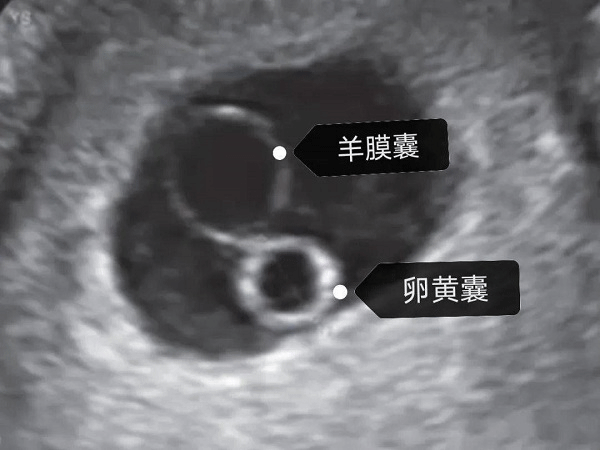

2 B超图

当孕囊平均直径在5-6mm时,通过阴道超声就可发现卵黄囊,正常来说,卵黄囊中央无回声,周边厚薄一致,边界清晰的环形高回声,具体如下图:

孕囊直径在5-6mm时可通过超声发现卵黄囊

A图白色箭头显示妊娠囊内的正常卵黄囊,黑色箭头表示胚胎,在其中还可见羊膜、羊膜囊、绒毛膜囊和卵黄管等组织,B图为经阴道超声显示妊娠第9周的存活胚胎以及卵黄囊。